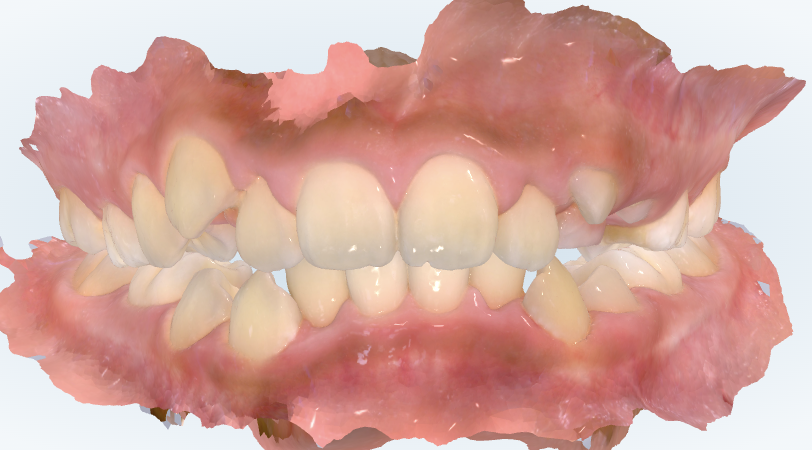

初診時の画像診断

前歯が出っ歯さん傾向でした。

上下の歯並びにガタガタがありました。

咬み合わせが深いです。

わかりました。スキャンした歯並びを見てみると、出っ歯の傾向はかなり強いです。理想は上下の前歯同士が当たって噛み切れる状態なのですが、今は前歯が当たっていません、下の前歯が上の歯ぐきに当たりそうな位置にいます。